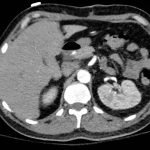

Chest x-ray and CT angiogram was performed to evaluate his thoracic and abdominal vasculature. Chest x-ray did not show any significant widening of the mediastinum. The CT angiogram demonstrated an intimal tear along the aortic arch separating a true and false aortic lumen, consistent with an acute aortic dissection. The true lumen (highlighted in blue in images 1-5) can be identified by continuity with an undissected part of the aorta1. While the false lumen (highlighted in red in images 1-5) can be identified by its crescent shape and larger cross-sectional area.1